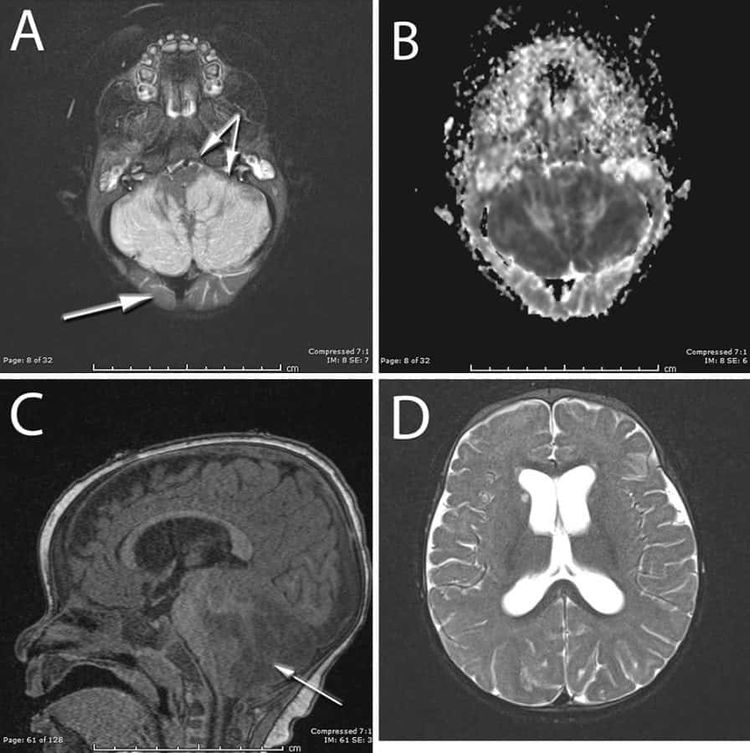

The baby was stiff and struggling for breath when she arrived at Riley Hospital for Children, Indianapolis. Scans revealed severe swelling in the bottom half of her brain.

This was blocking the normal flow of cerebrospinal fluid – a critical condition that causes rapid death. A drain was fitted to divert the fluid, prior to the skull operation. The bone was not replaced.

The infant’s neurological condition slowly improved, and life support was removed six days later. In two weeks she was participating in rehabilitation exercises and the drain was replaced with a small tube implant.

Six months later brain scans showed the cerebellum, which coordinates and regulates muscle movement, was irreparably damaged.

But her coordination was normal and, other than a minor speech delay, she was meeting all appropriate developmental milestones.